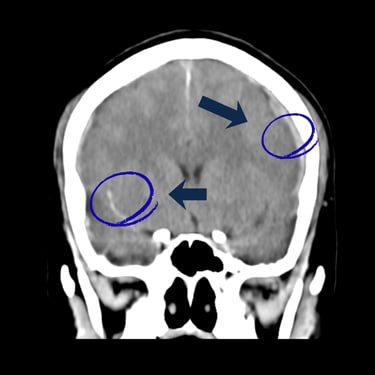

El trauma craneal severo es una de las principales emergencias neurológicas y puede poner en riesgo la vida del paciente. El diagnóstico por imágenes, a través de tomografía computarizada o resonancia magnética, es fundamental para identificar hemorragias, fracturas o lesiones cerebrales y definir el tratamiento adecuado. La evaluación temprana y la intervención oportuna por parte del neurocirujano permiten reducir complicaciones y mejorar el pronóstico neurológico. Una atención especializada y multidisciplinaria resulta esencial para garantizar la recuperación y preservar las funciones cerebrales.